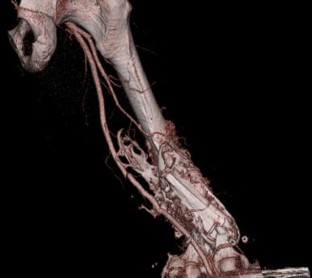

Fig. 1

Fig. 2

Fig. 3

Fig. 4

Fig. 5

Fig. 6